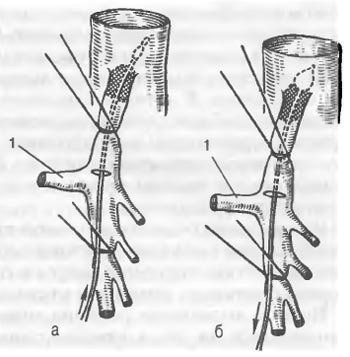

Іноді хірургія – єдиний вихід. Звільнити артерію від стискання – завдання не з легких, проте можливе. Сучасні методи дозволяють забезпечити ефективний результат.